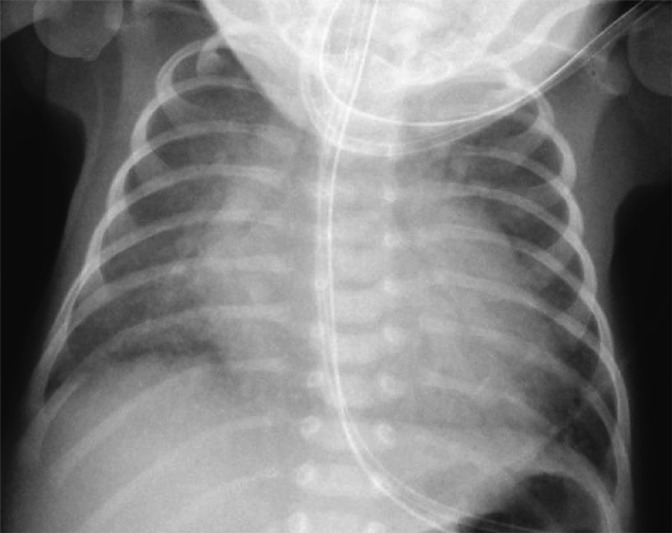

A female baby was delivered by an emergent cesarean section secondary to fetal bradycardia at a gestation of 33 weeks and 4 days. She weighed 1,700 g, and was eventually referred to our hospital at 12 days old. During pregnancy, her mother was doing well without detection of any congenital anomaly including heart disease on routine fetal ultrasonograms. She had no family history regarding congenital heart disease. She was suffering from progressive respiratory distress and congestive heart failure. Levine 2/6 continuous murmur was heard at the left sternal border of the second intercostal space. Her heart rate, respiratory rate and blood pressure were 164 beats/min, 70 breaths/min and 60/30 mmHg, respectively. Oxygen saturation was 99% on room air. Chest X-ray showed cardiomegaly with right pulmonary plethora (Fig. 1). An electrocardiogram showed biatrial overload. Her serum B-type natriuretic peptide level was 3,383 pg/mL. The RPA originated from the left posterior aspect of the proximal AAo. The orifice of the RPA at the proximal AAo was 5.0 mm. Moreover, the RPA was connected to the PT via a 2.0 mm-diameter lumen at the intrapericardial portion adjacent to its aortic origin. She was diagnosed as having AORPA, left aortic arch, patent ductus arteriosus bridging normally between the aortic arch and the PT, and patent fossa ovale by transthoracic echocardiography and computed tomography (Figs. 2, 3). Nitrogen inhalation therapy was started to treat high pulmonary flow.

Fig. 1 Preoperative chest X-ray showed cardiomegaly and right pulmonary plethora